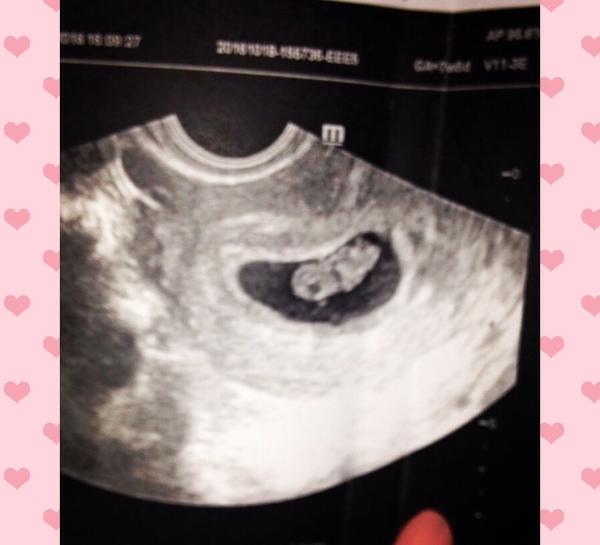

Dakujeme krasne❤️